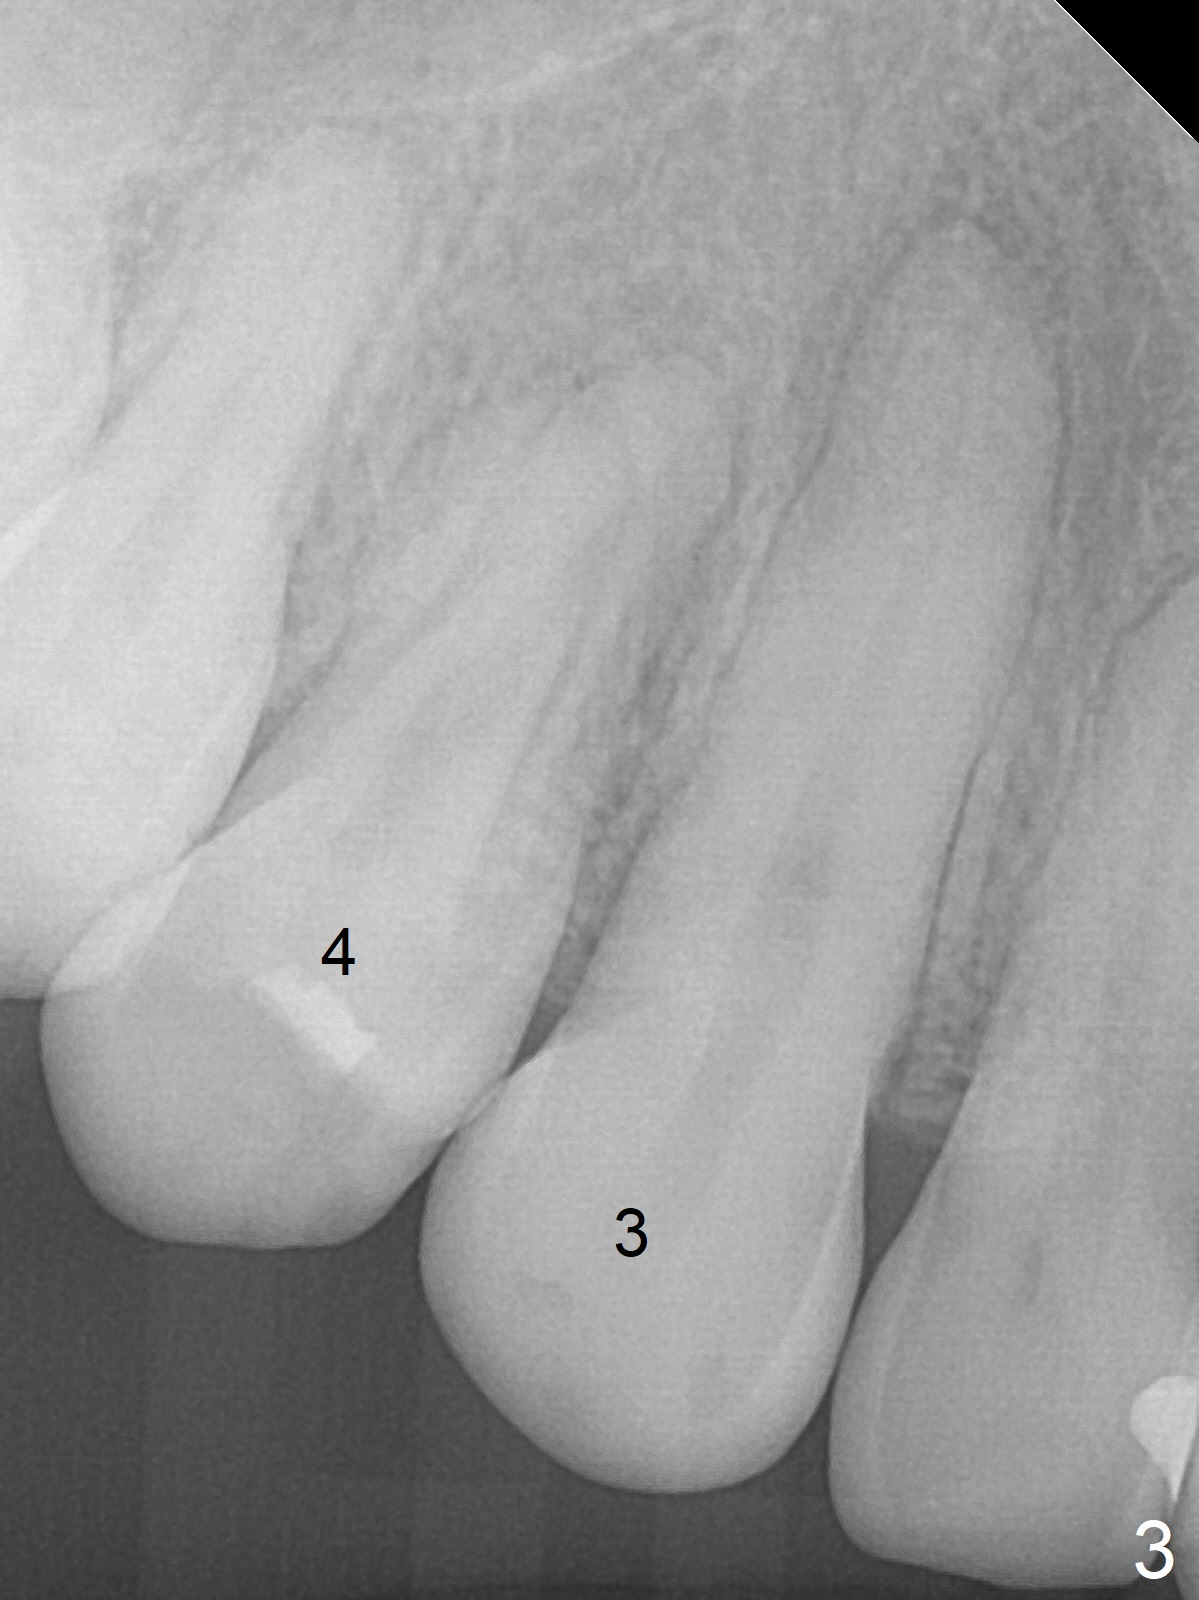

Discoloration of Upper Canines and

1st Bicuspids

Five months post debanding, the upper right canine becomes transiently symptomatic (tender to touch). Although both the right (Fig.1) and left (Fig.2) canines (3) and 1st bicuspids (4) discolor, the right ones are necrotic (pulpal test). It appears that these two teeth have periapical radiolucency (Fig.3,4), while the lateral incisor has shortened root (2). The longest tooth (upper canine) appears to be the most vulnerable to trauma associated with orthodontic movement.